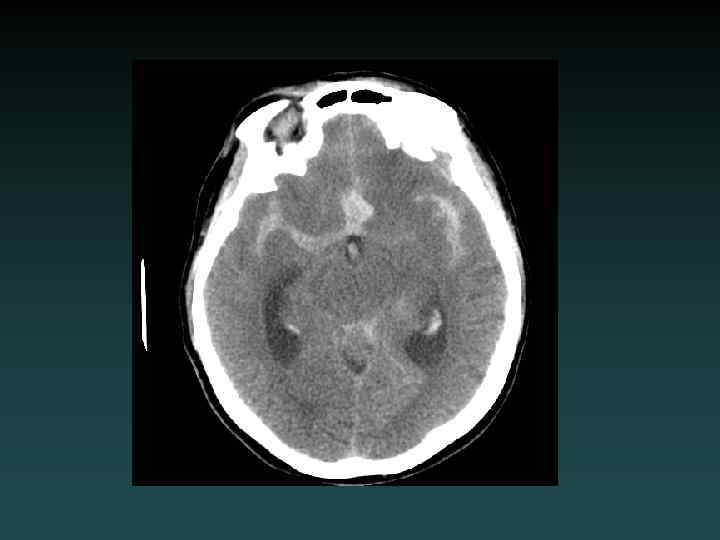

Subarachnoid Hemorrhage • Subarachnoid – Sulci – Cisterns – Ventricles • Trauma – lateral convexities • Aneurysm – basal cisterns • Interpeduncular Cistern – most sensitive

Aneurysmal SAH • Sudden severe headache • HYPERDENSE CSF spaces • Location – Interhemispheric: ACo. A – Sylvian: MCA • HYDROCEPHALUS, VASOSPASM and ISCHEMIA – MUST find the aneurysm! • DSA, CTA and/or MRA